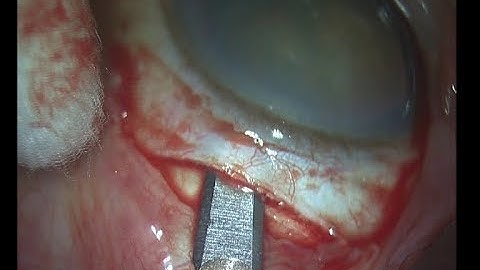

White cataract phaco for beginners Part 1 Soosan Jacob with audio 5 min